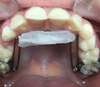

CIRE QUADHELIX